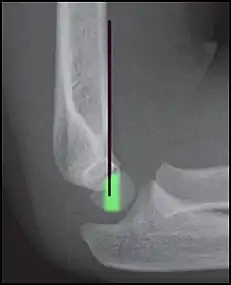

- Anterior humeral line (black line), with normal area passed on the capitulum of the humerus colored in green in a 4 year old child.[9]